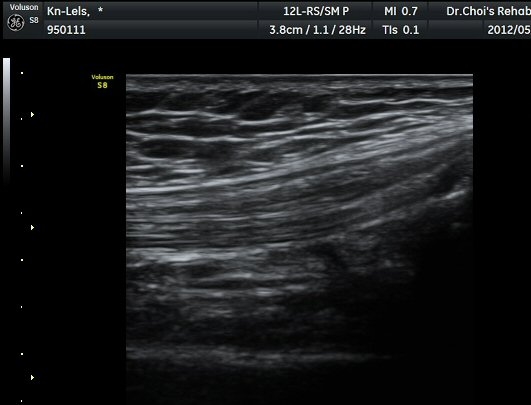

»çµÎ±Ù ÈûÁÙ Á¾´Ü¸é°Ë»ç¿¡¼­ ÈûÁÙÀÇ ºñÈİ¡ °üÂûµÈ´Ù9±×¸² 1, 2).